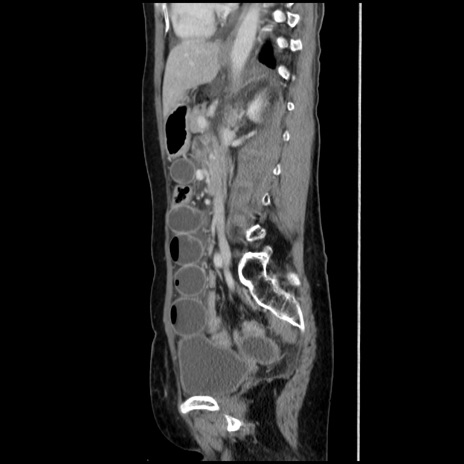

症例32(矢状断像)

【症例】40歳代 女性

【主訴】上腹部痛、嘔気・嘔吐

【現病歴】約9時間前頃から急に上腹部痛、嘔気、嘔吐が出現。改善しないため救急要請。

【既往歴】子宮頚癌(広汎子宮全摘術、放射線療法)、腸閉塞

【身体所見】腹部:平坦、軟、腸雑音亢進、上腹部を中心に腹部全体に圧痛あり。

【データ】WBC 8400、CRP 0.03